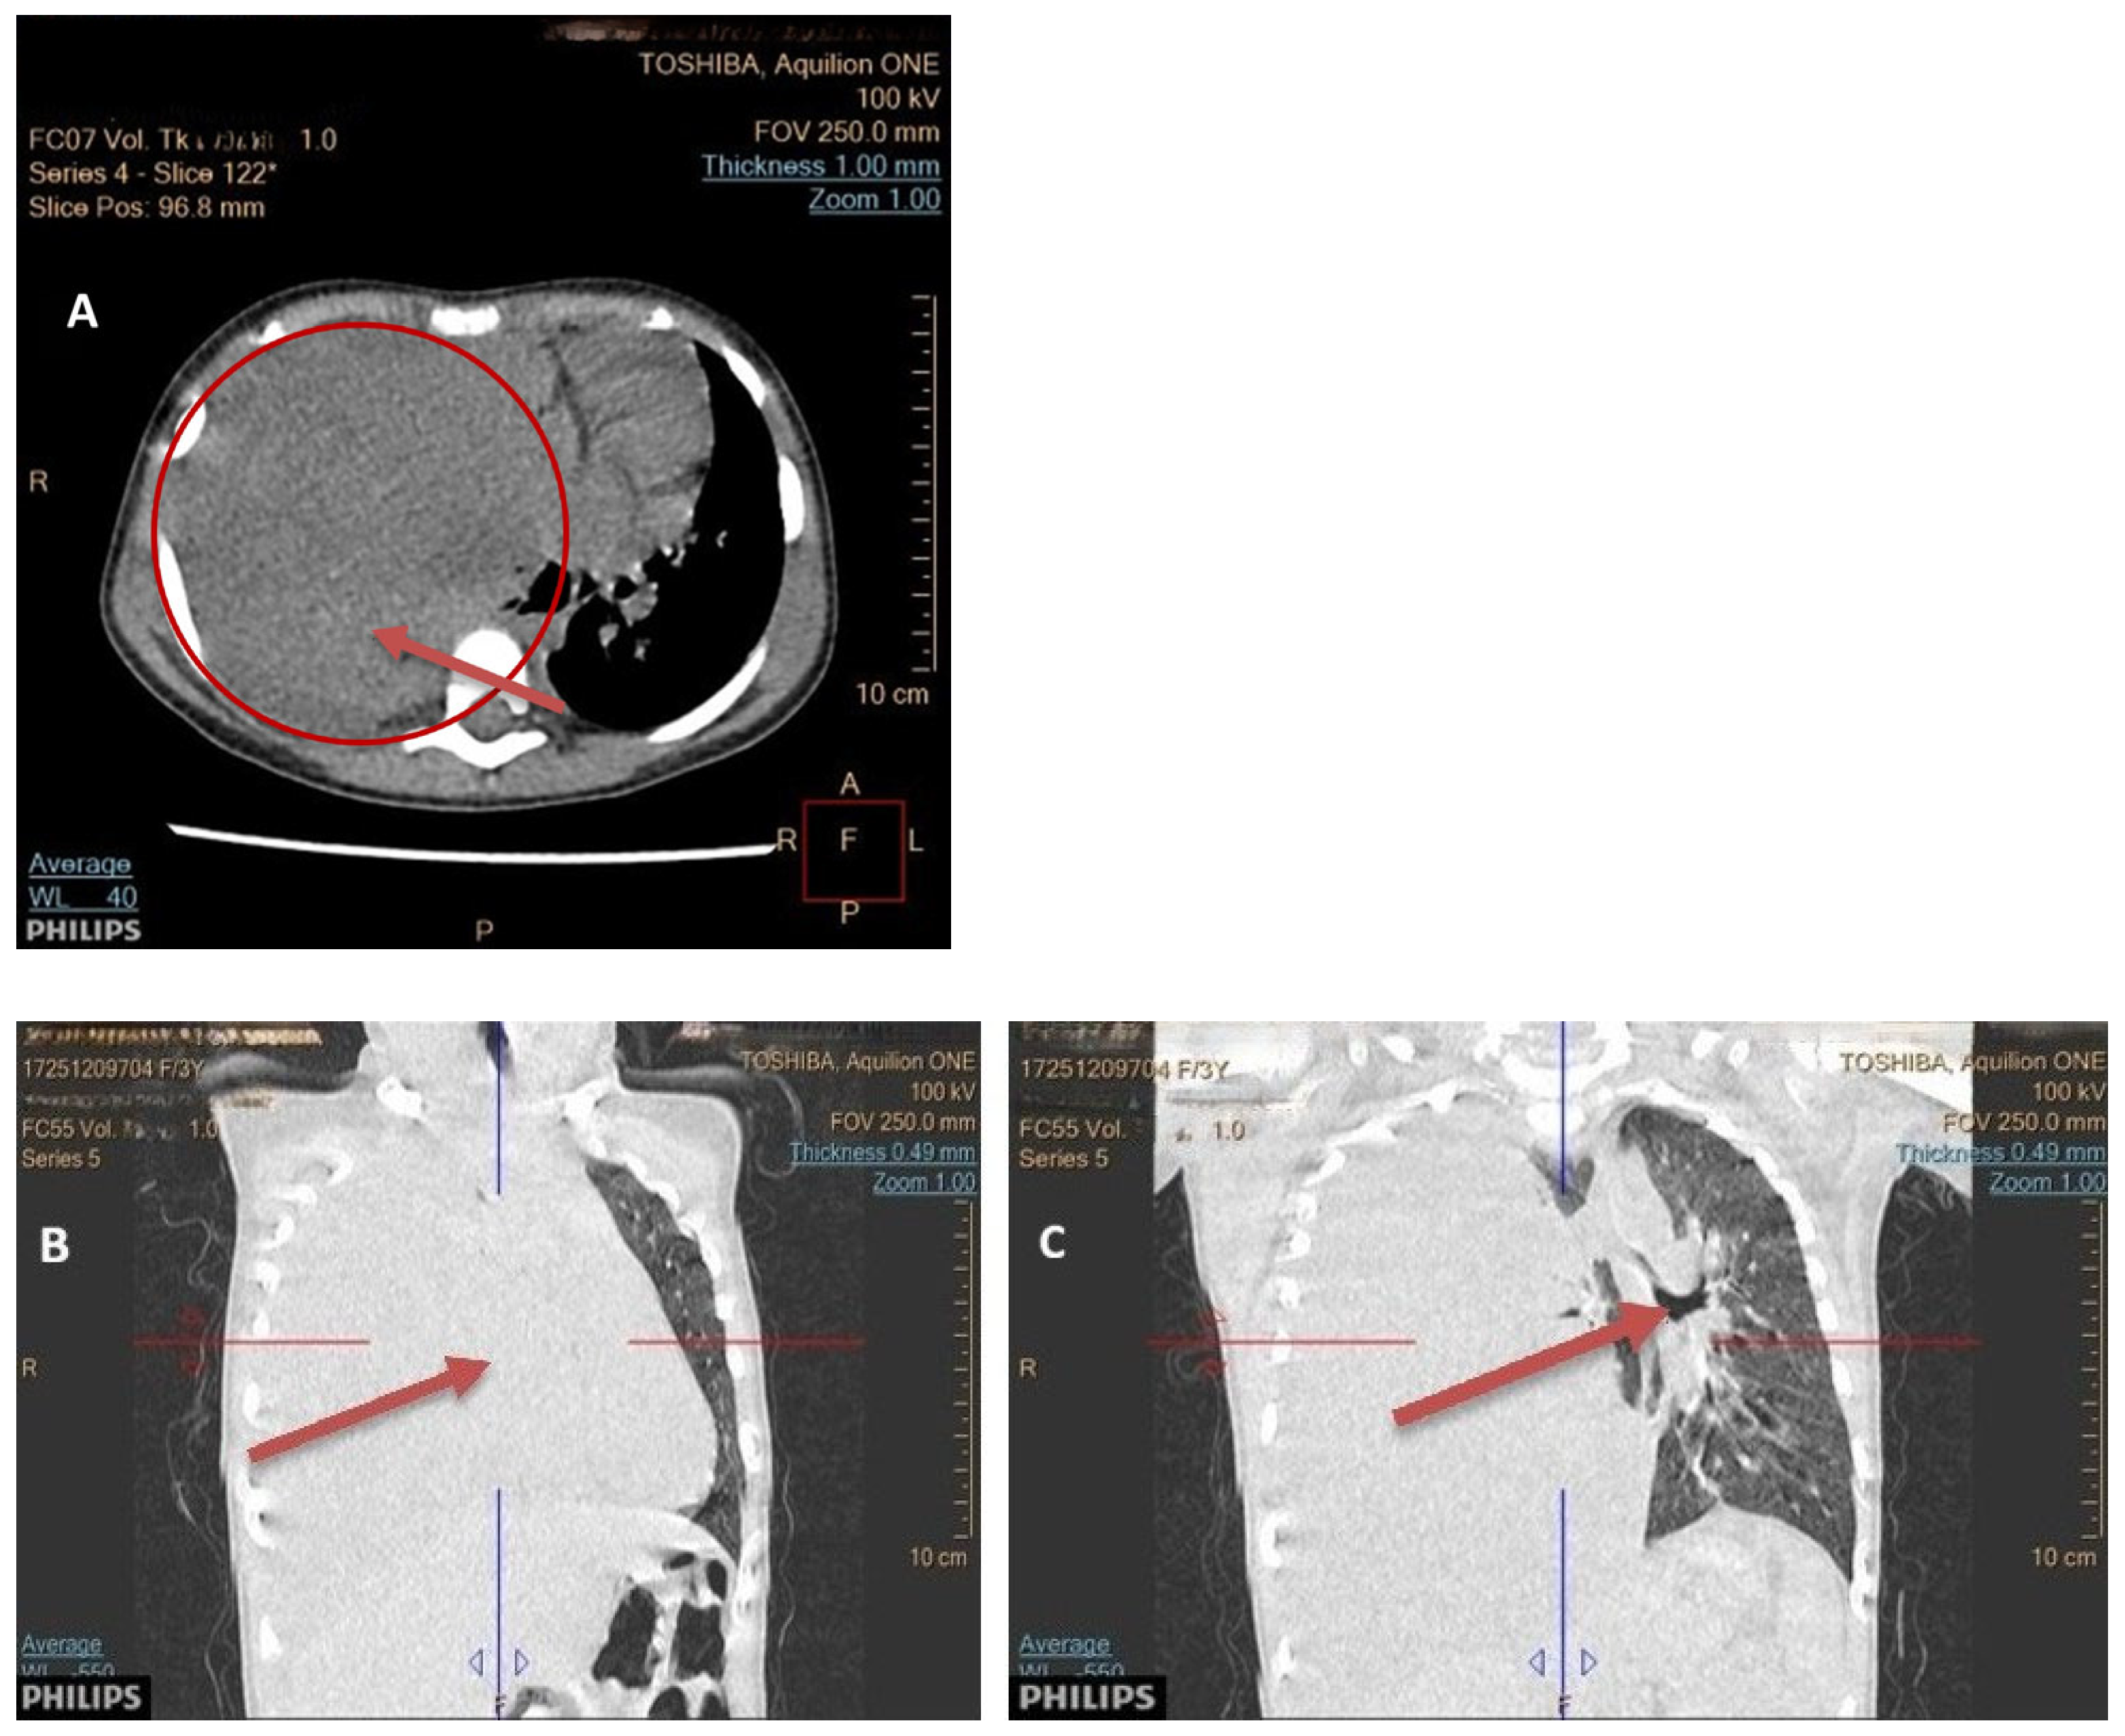

Seven children had a tumor located on the left side of the chest, and eight children on the right side. In seven children, the dimensions of the tumor were >10 cm; in five, they measured 5–10 cm; and in two patients, they were below 5 cm. In one patient, the dimensions were difficult to assess due to the occurrence of a massive pneumothorax. No bilateral lesions were found. Typical radiological findings are shown on Figure 2, Figure 3 and Figure 4.

Figure 2. (AC) A computed tomography imaging revealing a large, solid mass, at 11 × 9 × 11 cm, in the right hemithorax (A). The right lung is compressed and completely atelectatic (B). Marked tracheal deviation and mediastinal shift to the left side is noted (C).